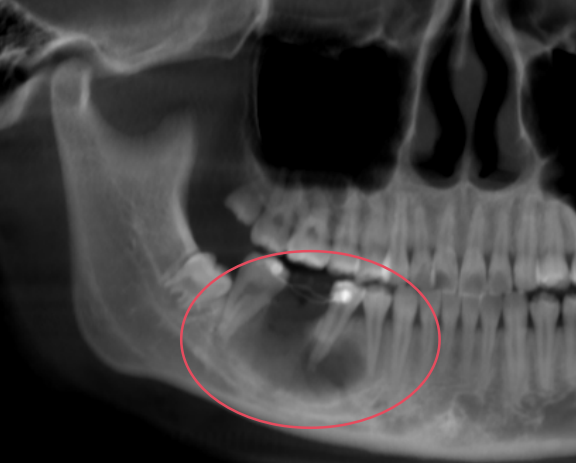

带着这份担忧,莉莉来到了烟台市口腔医院。经过详细检查,医生发现她的面部外形对称,口腔内右下后牙区域外观正常,没有红肿或溢脓。然而,进一步拍摄的曲面断层片却揭示了问题的严重性:影像显示她下颌骨内存在一个约30*12*15毫米的椭圆形囊性病变,边界清晰,这个囊肿已经累及多颗牙齿的根尖区域,并且紧贴下颌神经管上壁。

面对这个紧邻重要神经的颌骨囊肿,医疗团队制定了精细的微创手术方案。在全麻下,医生为她施行了“右下颌骨囊肿开窗减压术”,同时拔除了已受影响的牙齿。手术顺利,术后病理检查确诊为“右下颌骨良性囊肿”。

令人欣慰的是,莉莉术后恢复良好,没有出现下唇麻木等神经损伤症状。经过一年的定期随访复查,最新的X光片显示她下颌骨缺损区域已经实现了良好的骨质再生,为后续的种植牙修复奠定了坚实基础。